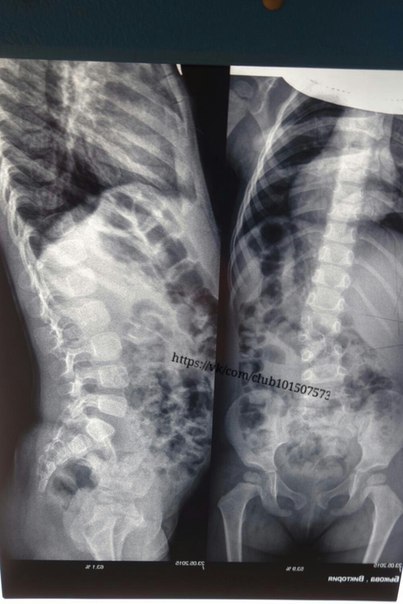

В мае 2015 года нашей маленькой дочке Виктории исполнилось 3 года и врачи поставили диагноз: сколиоз 2 степени (клиновидный позвонок L2). Мы обращались в известные клиники г. Москвы, Санкт-Петербурга и других городов, признанные одними из лучших в России. Везде нам подтвердили диагноз и рекомендовали своевременно и оперативно лечиться. О данной болезни много информации в интернете, поэтому кратко. Болезнь связана с позвоночником. В нашем случае это не приобретенный сколиоз, а врожденный, который требует незамедлительного лечения и оперирования. Без своевременного лечения дальнейшее прогрессивное развитие болезни у детей ведет к серьезным заболеваниям сердца, легких, нервной системы и т.д., в конечном итоге образованию горба, инвалидности, и сокращению продолжительности жизни, особенно у девочек. Каждый день болезнь прогрессирует и без своевременного профессионального лечения не отступит.

В мае 2015 года нашей маленькой дочке Виктории исполнилось 3 года и врачи поставили диагноз: сколиоз 2 степени клиновидный позвонок L2. О данной болезни много информации в интернете, поэтому кратко. Болезнь связана с ростом в позвоночнике дополнительного клиновидного позвонка, в связи с чем развивается сколиоз Без своевременного лечения и оперирования позвоночника дальнейшее прогрессивное развитие болезни у детей ведет к серьезным заболеваниям сердца, легких, нервной системы и т.д., в конечном итоге образованию горба, инвалидности, и сокращению продолжительности жизни.